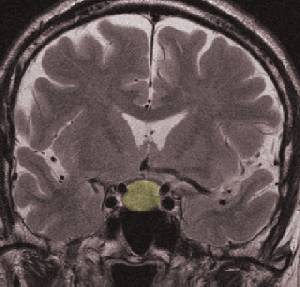

Pituitary Tumors and Radiosurgery

pituitarygk.jpg (8430 bytes)

Pituitary adenomas are very common neoplasms, constituting between 10 and 20% of all primary brain tumors. Historically, the treatment armamentarium for pituitary adenomas has included medical management, microsurgery, and fractionated radiotherapy. More recently, radiosurgery has emerged as a viable treatment option.

Radiosurgery has a role in the treatment of pituitary adenoma patients and causes a faster fall in secretory hormone product than conventionally fractionated radiotherapy. However, the exact place of radiosurgery as primary radiation therapy has yet to be defined. there is a role in the primary therapy but probably for the small, discreet tumors away from the chiasm and particularly those extending laterally into the cavernous sinus.